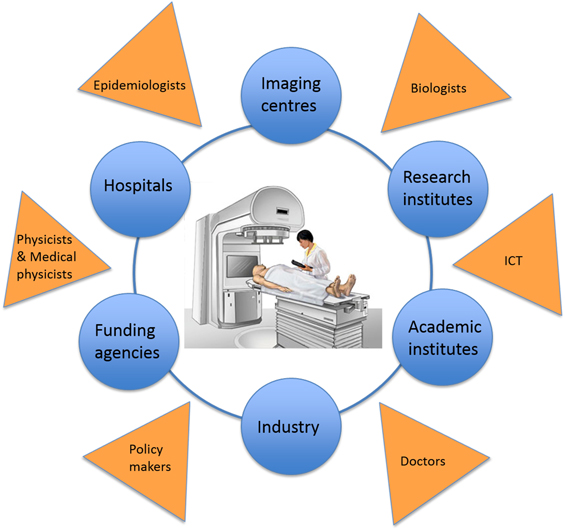

ENLIGHT: collaboration is key

By 2001, a number of projects were planning to build ion-therapy treatment centres in Austria, France, Germany, Italy and Sweden. There was therefore a clear opportunity to create a network that would allow the different project groups to work together, and to collaborate with other partners who could offer expertise or who might be interested in developing their own projects. After all, harnessing the full potential of particle therapy requires the knowledge and skills provided by physicists, physicians, radiobiologists, engineers and information technology experts, as well as collaboration between academic, research and industrial partners (figure 8).

Figure 8. ENLIGHT is a multidisciplinary network that brings together physicists, physicians, radiobiologists, engineers and information technology experts, and one of its key purposes is to enable collaboration between academic, research and industrial partners in particle therapy.